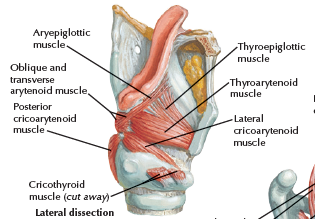

Muscle

關閉 Epiglotticus

- Thyroepiglotticus m

- Aryepiglotticus

Vocal fold

Motor: Recurrent laryngeal n.

- Arytenoid m.

- Transverse fiber / Oblique fiber

- Vocal fold adduction

- Post. cricoarytenoid

- Vocal fold abduction

- Lateral cricoarytenoid m.

- Vocal fold adduction

- Thyroarytenoid m.

- Arytenoid cartilage 往前

Motor: External laryngeal n.

- Cricothyroid m.

Nerve

- Sup. laryngeal n.

- Internal br.(Internal laryngeal n.)

- Sensor

- 穿過 Thyrohyoid ligament

- External br.

- Motor

- Internal br.(Internal laryngeal n.)

- Recurrent laryngeal n.

- Inf. laryngeal a.伴行

- 過Cricothyroid joint改叫Inf. laryngeal n.